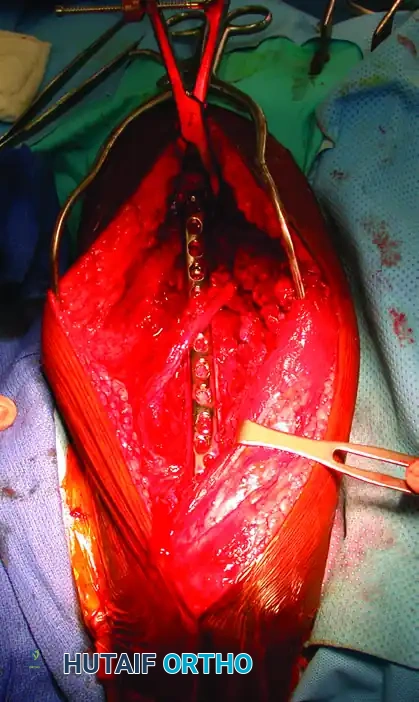

Deep Dissection and Fracture Exposure

- With the radial nerve protected (often using a vessel loop, though care must be taken not to apply excessive traction), incise the triceps off the periosteum to expose the humeral shaft.

- Biomechanical Imperative: Preserve as much of the periosteum as possible. Excessive periosteal stripping devascularizes the fracture fragments, significantly increasing the risk of nonunion.

Fracture Reduction and Provisional Fixation

- Place a single bone clamp (e.g., a pointed reduction forceps or Verbrugge clamp) on the proximal and distal fragments. Ensure these clamps are placed far away from the fracture site to control the fragments and simultaneously reflect the triceps.

Definitive Plate Osteosynthesis

- Select a large-fragment (4.5 mm) narrow dynamic compression plate (LC-DCP) or locking compression plate (LCP).

- Apply the plate to the posterior or posterolateral surface of the humerus. Depending on the fracture pattern, the plate should function in neutralization (if a lag screw is used), compression (for transverse fractures), or bridge-plating mode (for highly comminuted fractures).

- Ensure the radial nerve rests safely adjacent to, or over, the plate without tension.

- Perform routine layered closure. Reapproximate the triceps fascia meticulously. Skin closure is performed over a closed-suction drain to prevent hematoma formation, which can compress the radial nerve.